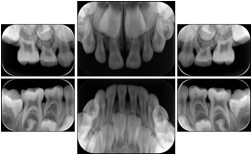

3. A patient in rural Minnesota experiences sudden vision loss and goes to a general ophthalmologist, who acquires OCT images and forwards them electronically along with a Structured Display to a retina specialist six travel hours away. The retina specialist is able to view the images in the standard layout that he is comfortable with, and to confirm that the patient has a choroidal neovascular membrane. He determines that is would be worthwhile for the patient to travel for treatment.

OCT Retinal Study with Cross Section and Navigation Structured Display

Figure OO-4. OCT Retinal Study with Cross Section and Navigation Structured Display